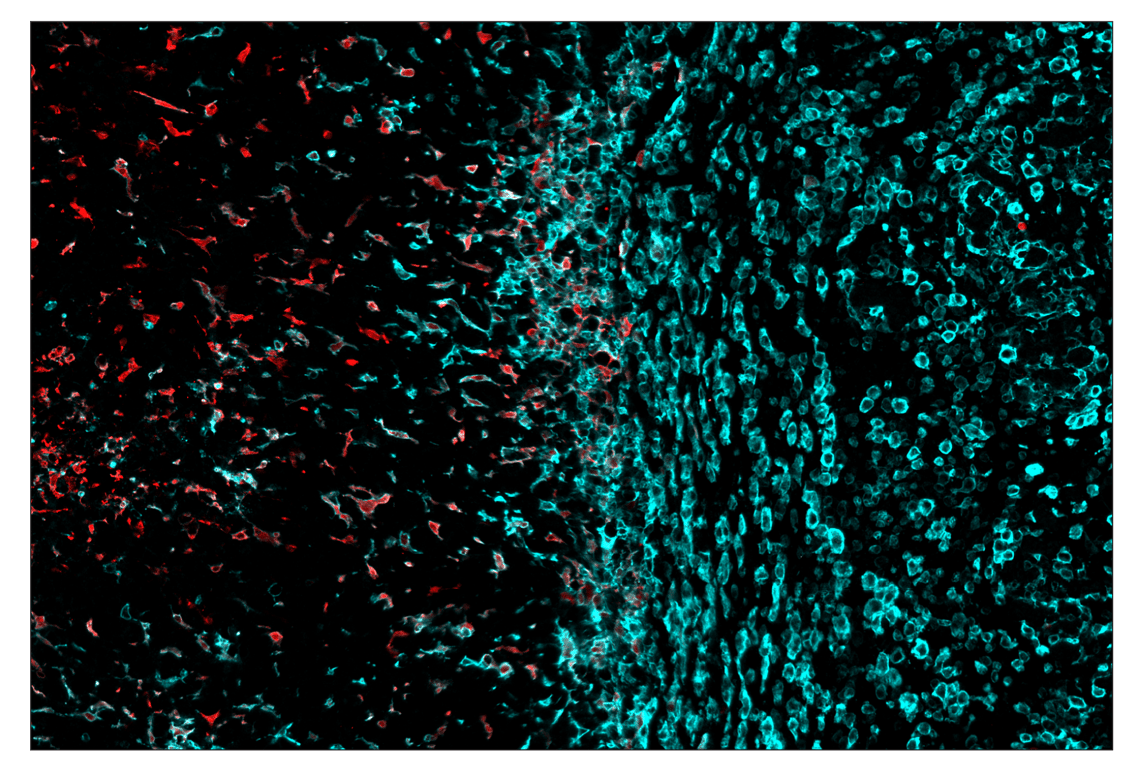

SignalStar™ multiplex immunohistochemical analysis of paraffin-embedded GL261 syngeneic tumor using Arginase-1 (D4E3M) & CO-0075-594 SignalStar™ Oligo-Antibody Pair #66757 (red) and F4/80 (D2S9R) & CO-0042-750 SignalStar™ Oligo-Antibody Pair #51924 (cyan). All fluorophores have been assigned a pseudocolor, as indicated. Staining was performed on the BOND RX autostainer by Leica Biosystems.

Immunohistochemistry Image 6: Arginase-1 (D4E3M) & CO-0075-750 SignalStar<sup>™</sup> Oligo-Antibody Pair